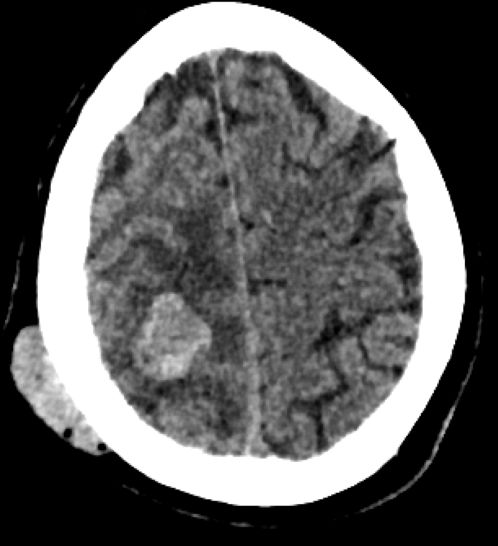

| Gehirn | Ein Jahr später wurde die Patientin krampfend und kollaptisch in der Wohnung aufgefunden. Ein CT ergab eine Hirnmetastase, die neurochirurgisch entfernt werden konnte.![]() |

![]() | |